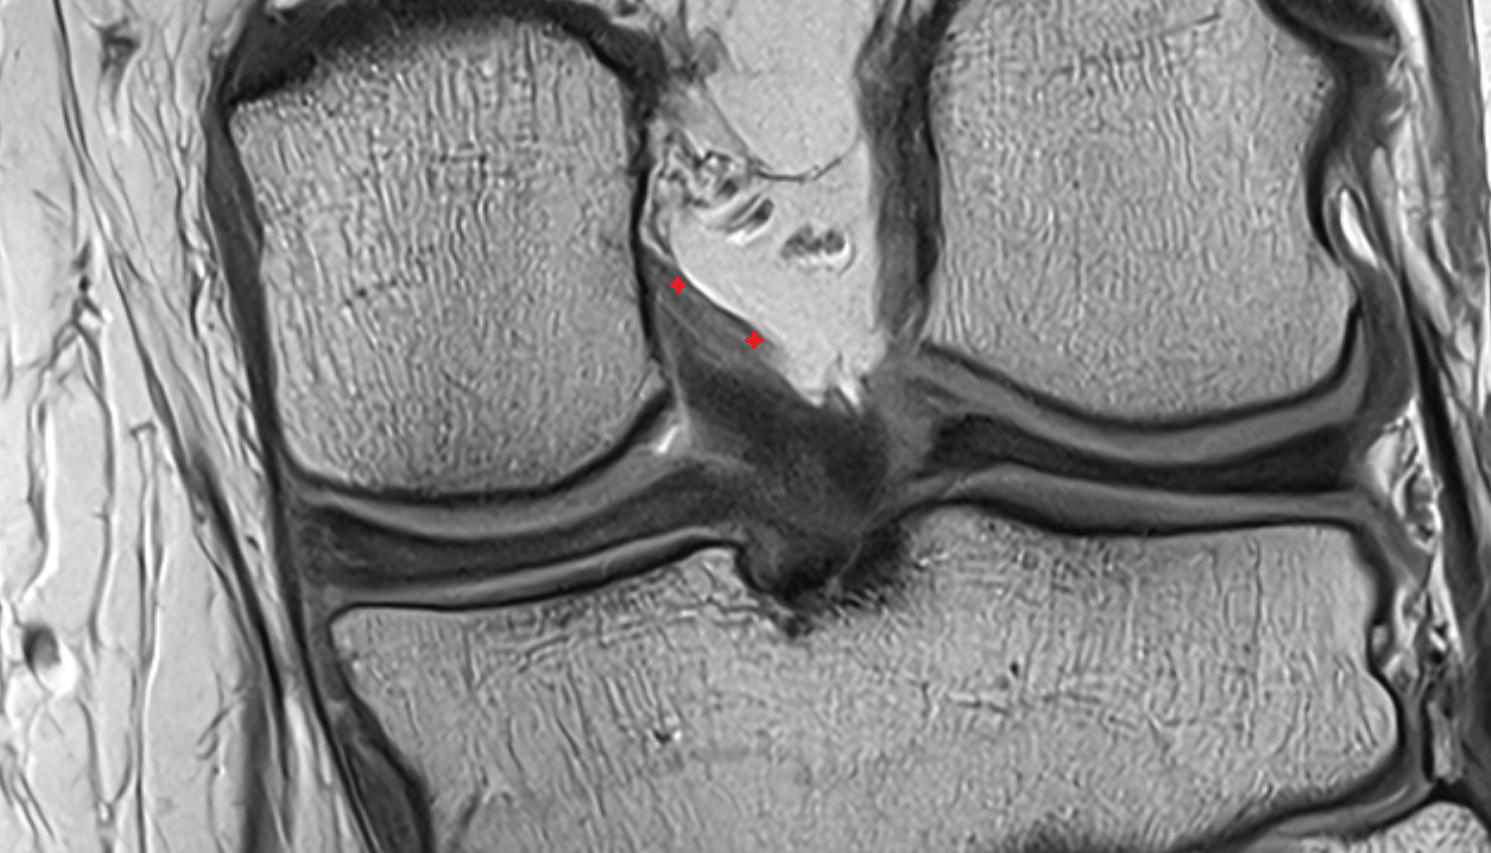

- Medial meniscus

- Lateral meniscus

- Anterior cruciate ligament

- Posterior cruciate ligament